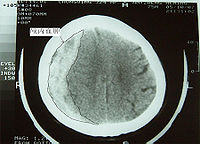

外伤性进展性颅内出血病变

原发性脑挫裂伤一般不需要手术治疗,但当有继发性损害引起颅内高压甚至脑疝形成时,则有手术之必要。对伴有颅内血肿30ml以上、CT示有占位效应、非手术治疗效果欠佳时或颅内压监护压力超过4.0kPa(30mmHg)或顺应性较差时,应及时施行开颅手术清除血肿。对脑挫裂伤严重,因挫碎组织及脑水肿而致进行性颅内压增高,降低颅压处理无效,颅内压达到5.33kPa(40mmHg)时,应开颅清除糜烂组织,行内、外减压术,放置脑基底池或脑室引流;脑挫裂伤后期并发脑积水时,应先行脑室引流待查明水原因后再给予相应处理。